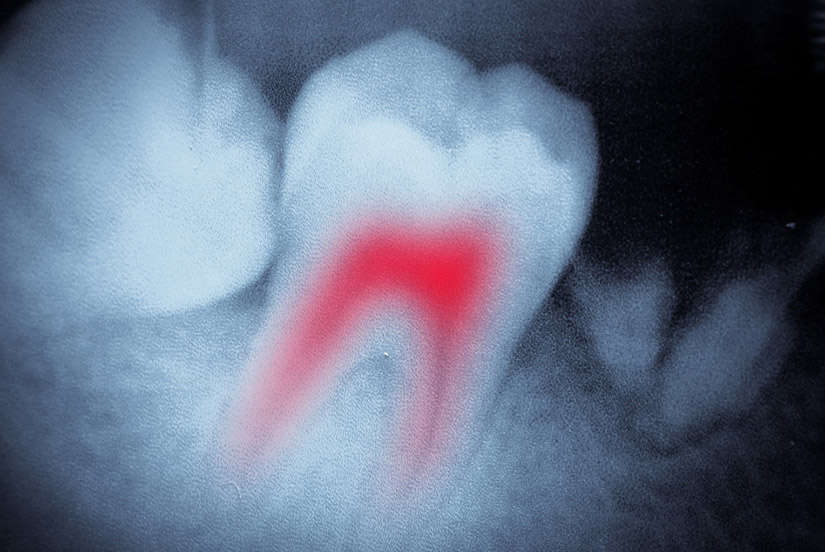

Endodontic treatment - root canal

x-smart drill Endodontics is the dental specialty that deals with the nerves of the teeth. Root canals are probably the most notorious procedure in dentistry and the most common procedure relating to endodontics. When a tooth becomes infected it is usually related to the nerves in the root of the tooth. The infected nerves need to be removed. If left untreated an infection can turn into an abscess, which is a much more serious problem that includes bone loss in the jaw.